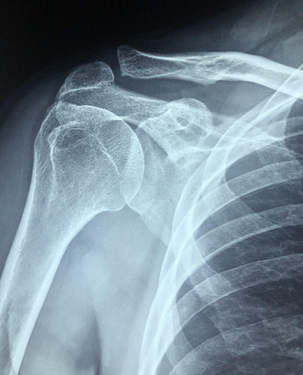

Hoy 8 de noviembre es el Día Mundial de la Radiología, lo cual nos recuerda el hecho de que los descubrimientos científicos muchas veces ocurren por mera casualidad, tal como sucedió con el científico alemán Wilhelm Conrad Roentgen, quien se encontraba experimentando con tubos de rayos catódicos y se dio cuenta que por medio de estos se generaban unos rayos misteriosos capaces de atravesar materiales sólidos dejando imágenes impresas en placas fotográficas, dado que el científico también era aficionado a la fotografía.

Y en ese entonces se le ocurrió también atravesar una de sus manos entre los rayos invisibles y la placa fotográfica obteniéndose por primera vez una radiografía donde curiosamente se veían bien definidos los huesos de la mano. Otras versiones cuentan que Roentgen le pidió a su esposa que pusiera la mano y se obtuvo una imagen donde el anillo se veía más oscuro que los huesos. Dicho descubrimiento fue un verdadero antes y después en el mundo de la medicina, y le valió el premio Nobel de física a su autor. Honor a quien honor merece. Imagínense, cómo harían los médicos de hoy para tratar problemas relacionados con traumatismos o enfermedades de los huesos si no tuvieran a la mano esta tecnología.